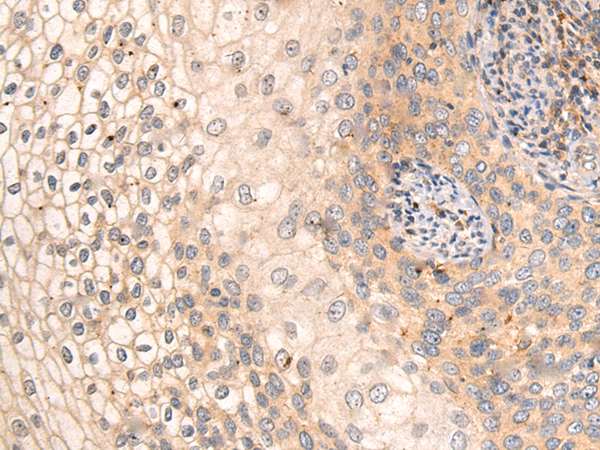

IHC positive control: |

Human thyroid cancer and Human liver cancer |

IHC Recommend dilution: |

15-50 |